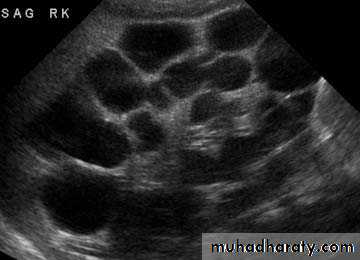

Most common cause of fetal hydronephrosis.

Obstruction at the junction between renal pelvis and ureter.Incidence: 1:1000

US: pre- and post-natal.IV Urography